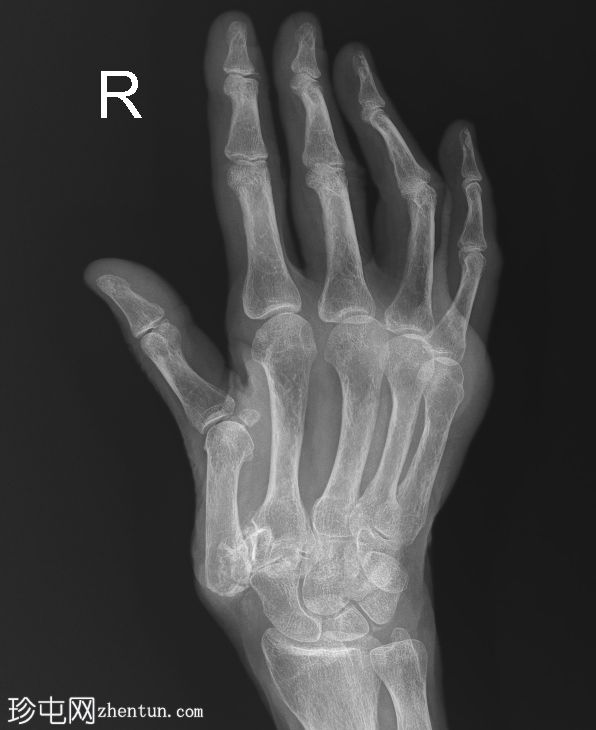

右手X线片

X线片

正位

斜位

小指近节指骨干轻微移位螺旋形骨折,周围软组织肿胀。怀疑拇指掌骨基底部和大多角骨骨折。

第一腕掌关节脱位,周围软组织肿胀。

第二至第五腕掌关节正常。桡腕关节、掌指关节和指间关节正常。尺骨茎突正常。

骨密度降低。